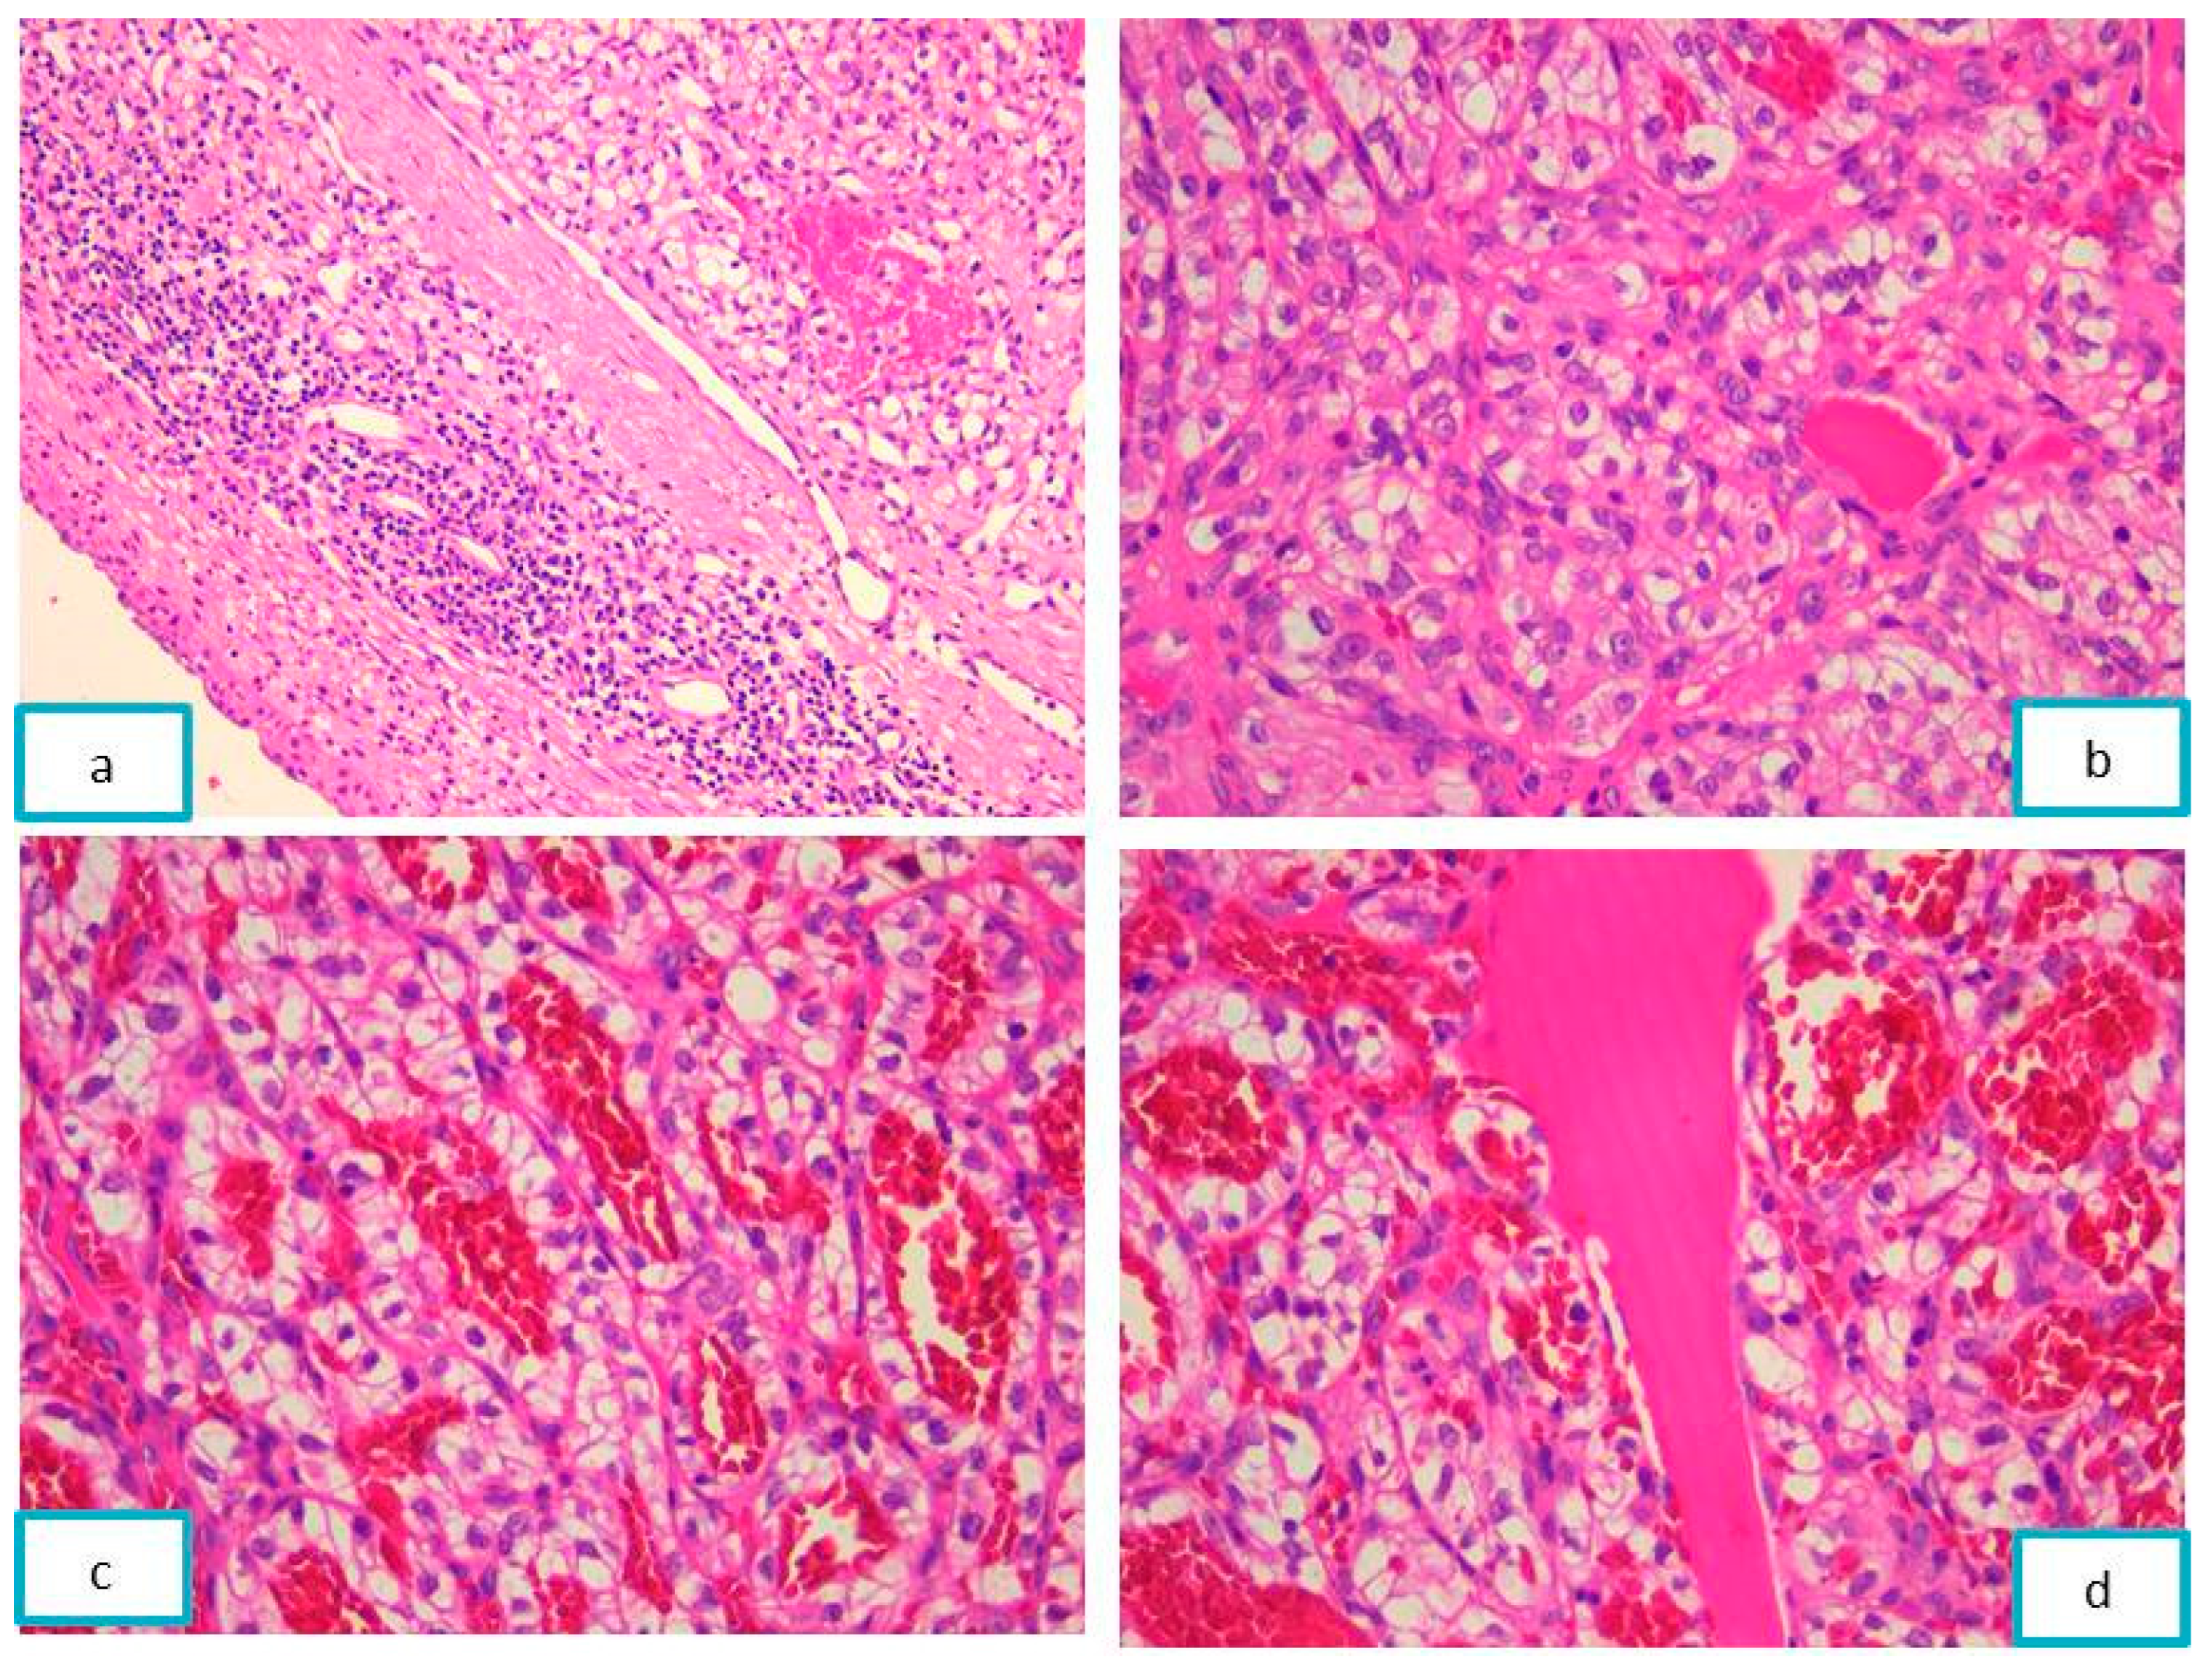

2.2.2. Pathological Findings

2.3.2. Pathological Findings